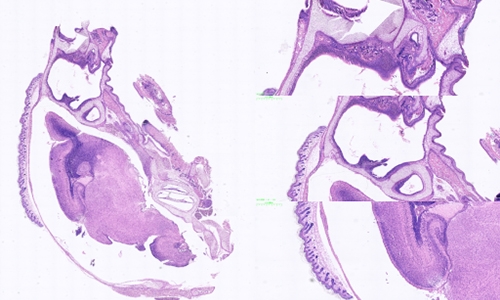

冰冻切片和石蜡切片是常见的组织学研究中的两种切片技术,它们在样本处理和切片制备过程中存在一些区别。

扫描切片

样本处理方面:冰冻切片主要适用于新鲜组织或不含脂肪的组织,如肌肉、肾脏和神经组织等。在进行冰冻切片前,组织样本通常被快速冷冻,并使用冰冻剂(如液氮)来保持样本的冷冻状态。而石蜡切片则适用于各种类型的组织,包括脂肪组织。在进行石蜡切片前,组织样本通常需要进行固定、脱水和浸泡等处理步骤,最后嵌入到石蜡块中进行切片。

切片制备方面:冰冻切片的制备相对较快速简便。在冰冻切片过程中,组织样本从冷冻状态转移到切片机上进行切割,通常需要使用冰冻切片机和低温切片刀来确保样本的冷冻状态。而石蜡切片的制备相对复杂。在石蜡切片过程中,需要将经过处理的组织样本嵌入到石蜡块中,然后使用石蜡切片机进行切割。由于石蜡具有一定的硬度,因此需要使用高速旋转的刀片来切割并得到薄片。

切片质量方面:冰冻切片相对于石蜡切片来说,切片质量可能稍差。由于冰冻切片的过程较快,切片的质量受到冷冻状态的影响,容易出现组织断裂、伪影和冰晶等问题。而石蜡切片在固定和浸泡处理后,组织样本得到更好地保护,切片质量相对较好。

切片的用途方面:冰冻切片主要用于快速初步观察和诊断,例如快速冰冻切片可以用于术中病理诊断。而石蜡切片则适用于各种组织学研究,包括光镜下观察、免疫组化染色和分子生物学研究等。

冰冻切片石蜡切片是两种常见的组织学切片技术,选择合适的切片技术取决于研究的目的、组织类型以及需要的切片质量。无论是冰冻切片还是石蜡切片,它们都为组织学研究提供了重要的工具和手段。